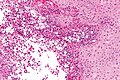

Features:[2]

- Macrophages - clear-to-foamy cytoplasm.

- Lymphocytes.

- Plasma cells.

DDx:

- Rosai-Dorfman disease - usu. has emperipolesis.[3]